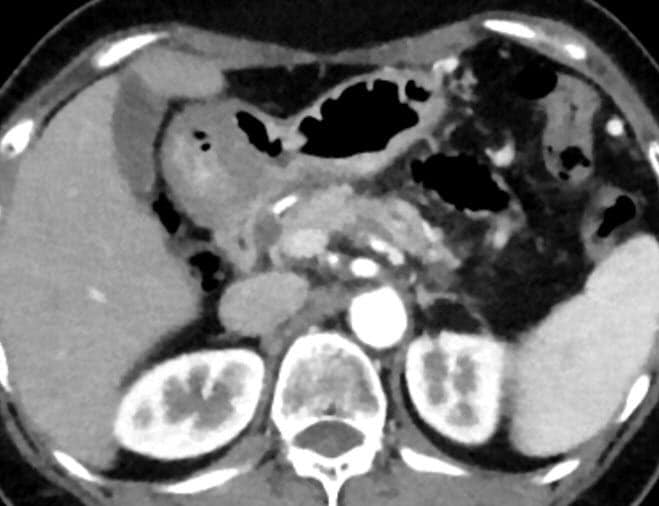

Post Graduate Institute of Medical Education and Research (PGIMER) “This is an exceptional IMR case as NCCT KUB was done at a radiation dose exposure (0.6 mSv) equivalent to Xray KUB and yet produced images with exquisite details. A tiny 3 mm calculus was seen in right kidney on IMR images which was not seen on other imaging modalities (USG, KUB) as well as on images produced by standard reconstruction. Hence low dose CT with IMR benefited this case to a great extent.”

India

Dr. Khandelwal & Team